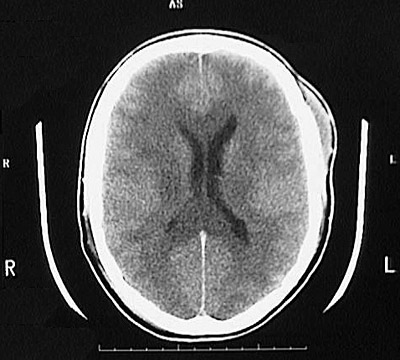

This is a normal head CT scan demonstrating the skull with the lateral ventricle and falx cerebri and frontal lobe and parietal lobe.